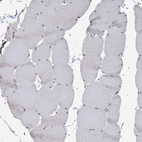

Immunohistochemical staining of human liver shows moderate cytoplasmic positivity in hepatocytes.